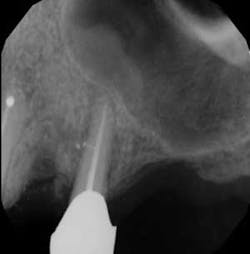

Each instrument and its accompanying technique have their own advantages and disadvantages. The key is to find a system to use in which all of the components are made to work together synergistically, such that they result in a procedure that is easy for the dentist to achieve the desired end results. In this instance, the desired end result is a debrided, clean canal that has been enlarged, shaped, and finished to receive a gutta-percha and sealed obturation (figures 1–4). This should be able to be achieved in an easy, quick, not too expensive, predictable, operator friendly manner. The dentist should not have to be Michelangelo to achieve the desired result consistently on every patient.